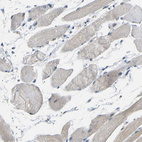

Immunohistochemical staining of human cerebral cortex shows moderate positivity in neuropil.